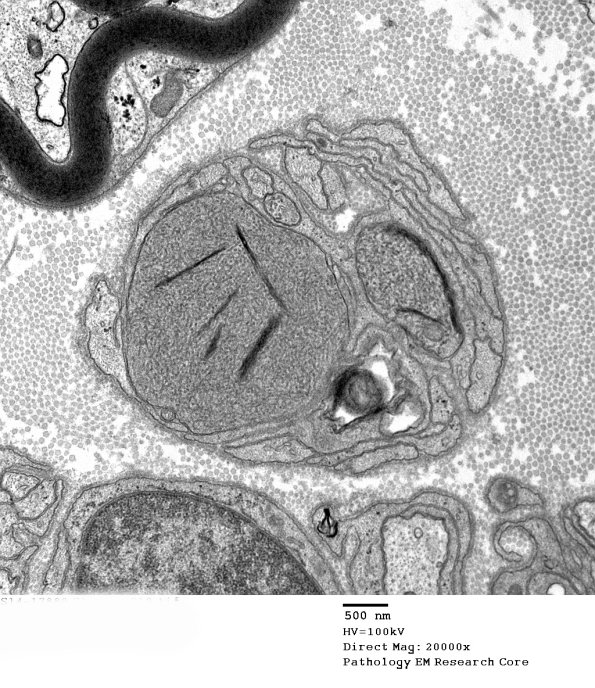

11B1 Axon, growth cone vs dystrophy (Case 19) EM 10 - Copy

11B1,2 Similar appearing dystrophic axons in another patient. (electron micrographs)